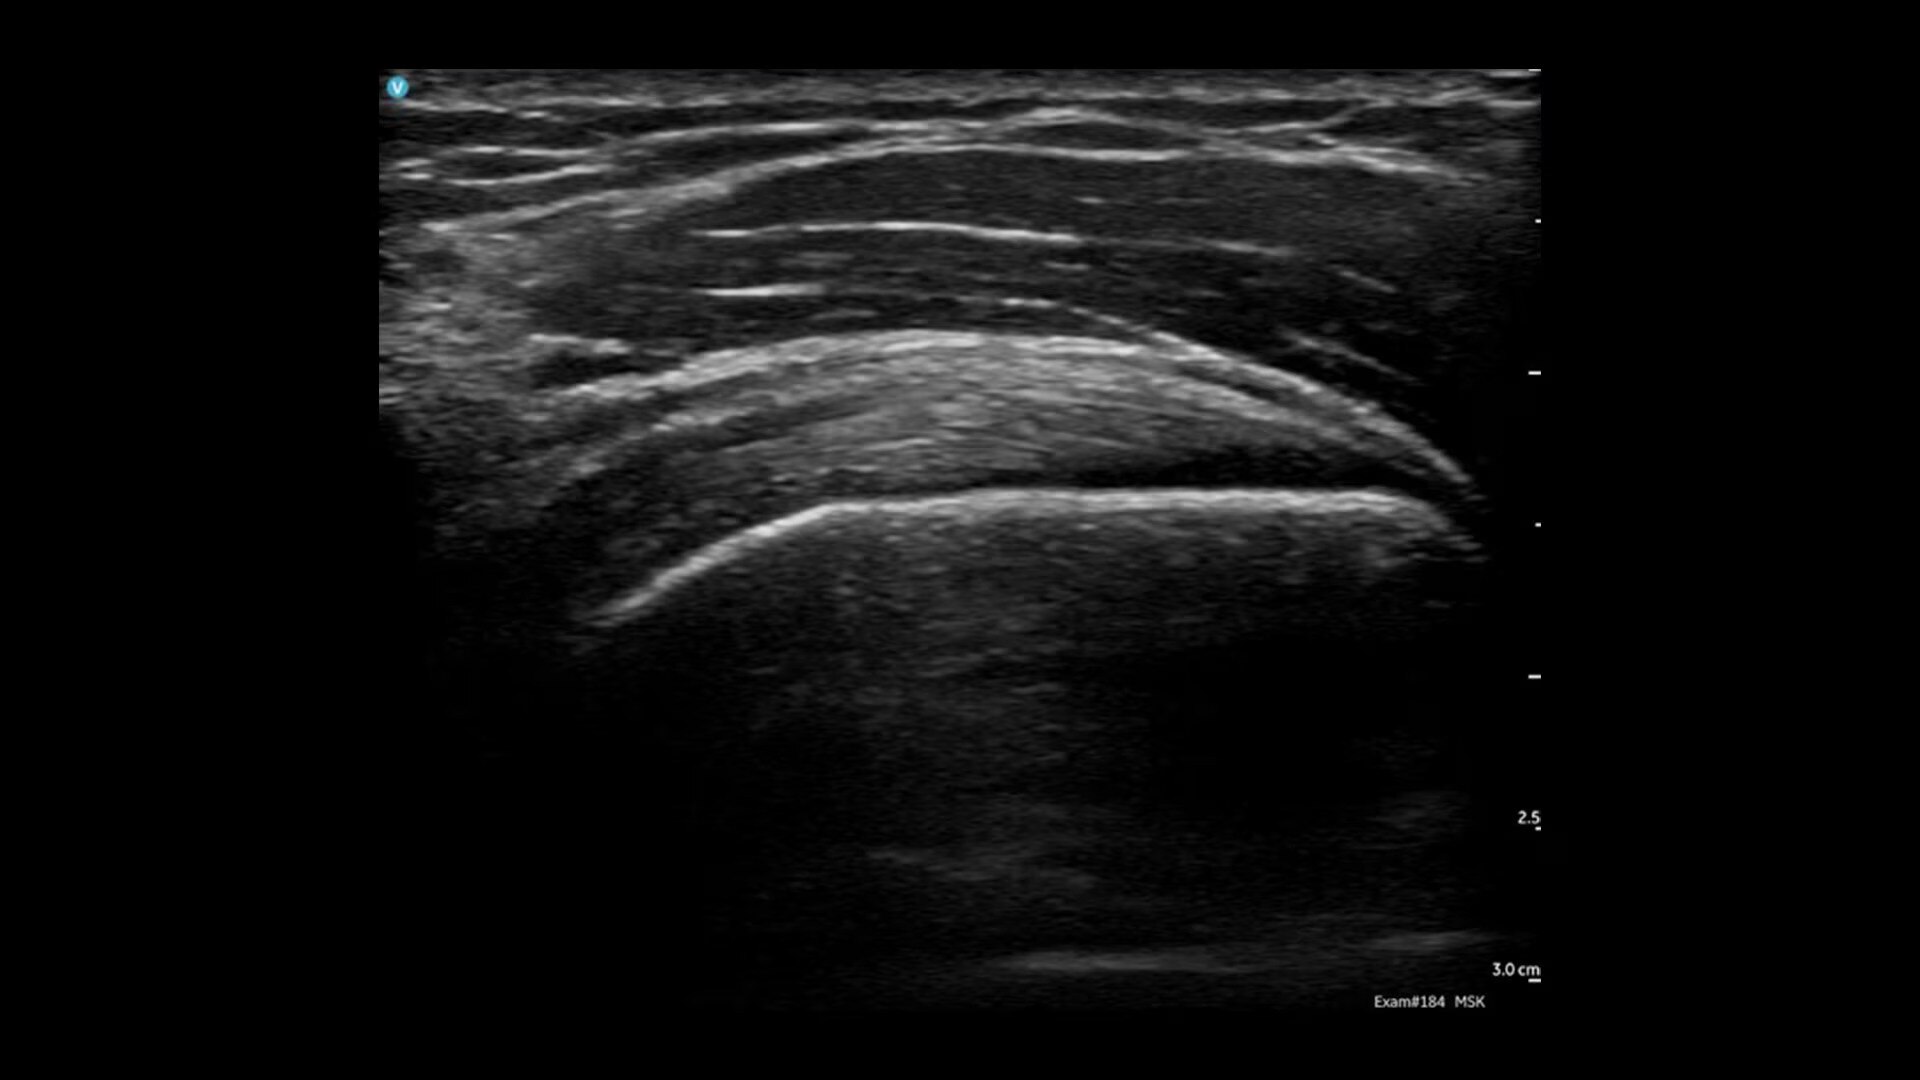

Vscan Air CL offers wireless freedom and maximum portability. One device delivers the value of two: the curved array transducer is ideal for abdominal imaging, obstetric assessments and more, and the linear array is ideal for vascular, MSK, lungs and more. Complete both shallow and deep scans with one device without compromising image quality.

Quality imaging capabilities for multiple clinical healthcare applications.

Ideal for OB/GYN, musculoskeletal, abdominal, lungs, and more. Complete both shallow and deep ultrasound scans with one probe without compromising image quality.

Image quality you can be confident in

Vscan Air leverages the power of our proprietary technology, SignalMaxᵀᴹ, to uniquely combine the miniaturization of hardware with the high transmit power of piezo electric crystals into a beautifully engineered small lightweight footprint for outstanding image quality. We take image quality one step further with our High-Definition Speckle Reduction Imaging (HD-SRI) for a boost in image quality that enhances details of images even more.

Key features for all users and specialties

Built for both new and experienced handheld ultrasound users with basic and advanced assessments in mind. Now including: B-mode; Color Doppler; PW Doppler; M-mode; and OB measurements.